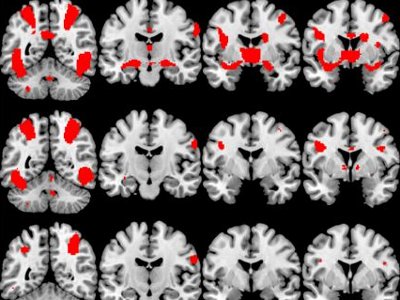

The healthy and “sex-addicted” groups were shown short videos of explicit porn and sports while their brain activity was monitored by functional magnetic resonance imaging, which measures blood-oxygen levels. The drug-addicted group substituted videos of people taking drugs instead of sexually explicit content.

They were. The fMRIs of those affected by sexual compulsion and drug addiction exhibited increased activity in three brain regions: the ventral striatum, dorsal anterior cingulate and amygdala. The first region processes reward and motivation, the second is responsible for anticipating rewards and establishing cravings and the third is the seat of emotional behavior and processing significant events.

[SIZE=1]Image: fMRIs showing activity in the brain of a person identified as “sexually compulsive.” The top row documents the subject watching explicit pornography. The middle row documents brain activity while watching erotic material, and the bottom row documents exciting sports.[/SIZE]